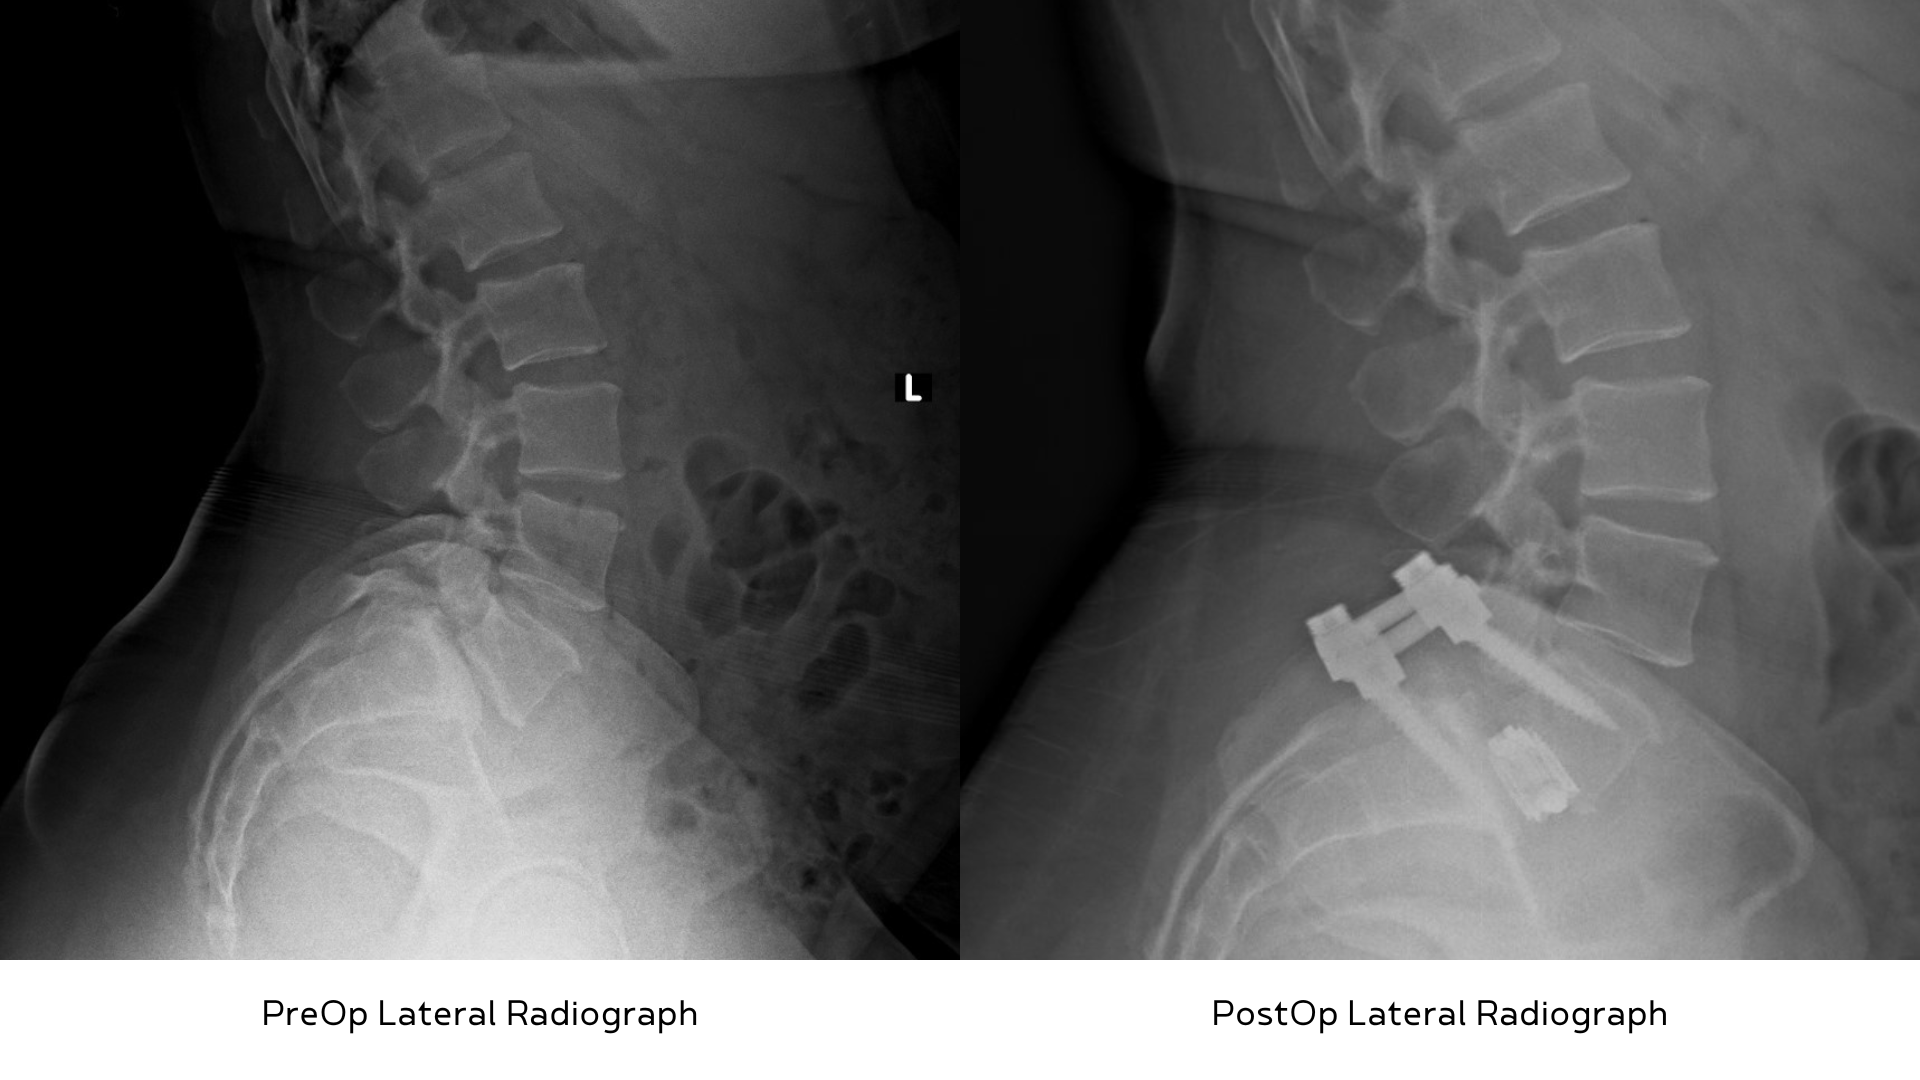

In my practice, I routinely use MISS for single-level lumbar microdiscectomy, lumbar laminectomy, and lumbar fusion. Using MISS versus a more traditional “open” technique has had a tremendous impact on my patients. For example, I recently performed a minimally invasive lumbar fusion at the L4-L5 level on an active woman in her mid-fifties. She had a condition called spondylolisthesis with stenosis which is a narrowing of the spinal canal. As a result, she was suffering from severe back and leg pain with progressive weakness. An avid golfer and pickleball player, she had not been able to do either for six months because of the worsening leg symptoms. I explained our surgical plan to perform the surgery using a Spinal Navigation System with the goal to shorten her recovery time. For comparison, a traditional “open” technique for the same surgery would generally result in a two-to-three-day hospital stay and return to full activity at three-to-four months. She was eager to proceed and get back to her active lifestyle. A few weeks later, she underwent a successful MISS decompression and fusion, and was discharged home from the hospital the following morning. By day seven, she no longer required pain medication. At her six week post operative visit in the office, she had fully recovered and was cleared for full activity.